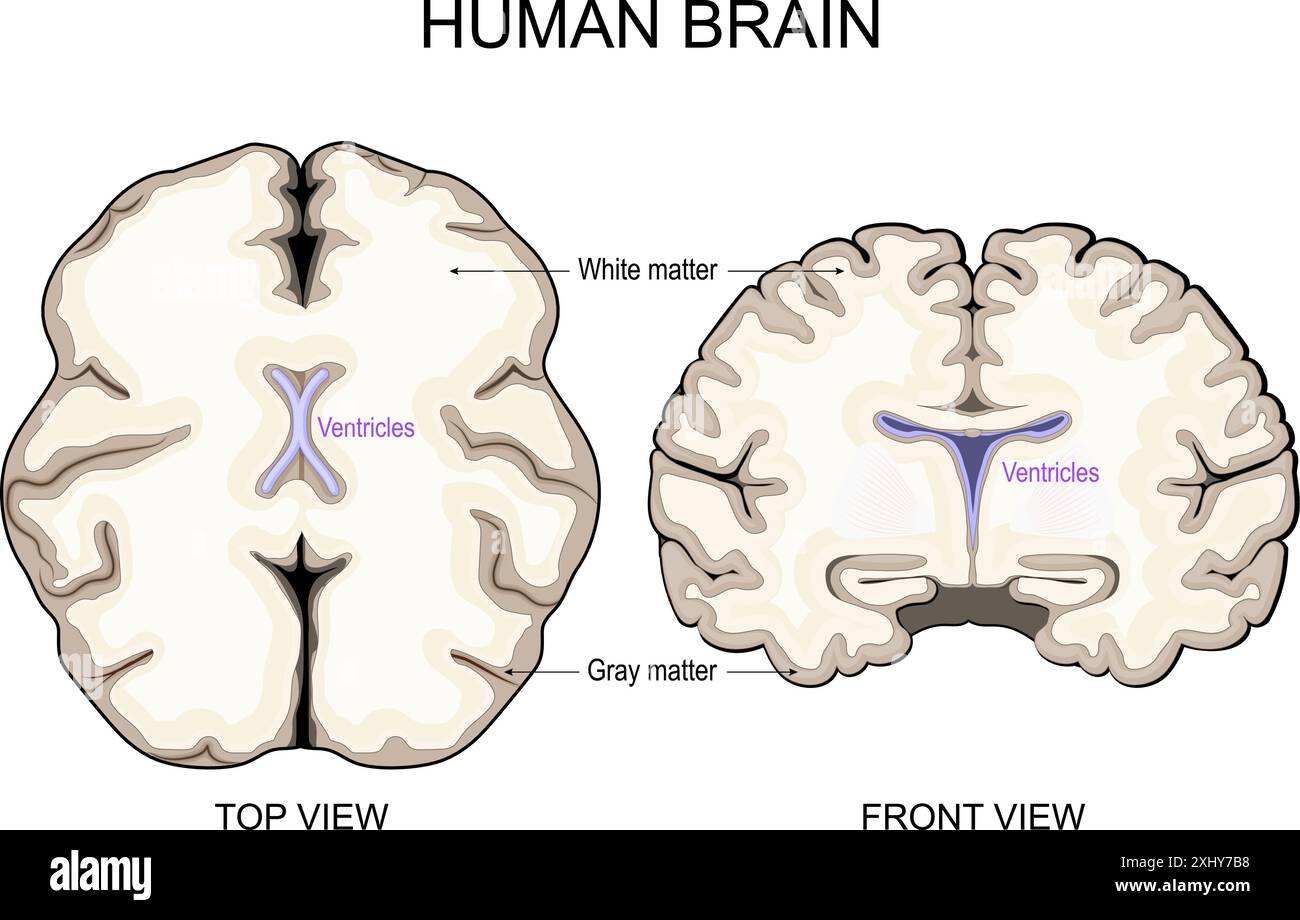

RF2XHY7B8–Anatomia cerebrale. Materia bianca e materia grigia. Corteccia cerebrale e ventricoli cerebrali con liquido cerebrospinale. Sezione trasversale di una vista frontale del cervello umano

RF2Y92GH4–Anatomia cerebrale. Vista frontale e sezione trasversale di un cervello umano. Primo piano dell'Hippocampus e dei ventricoli. Corteccia cerebrale. Illustrazione vettoriale